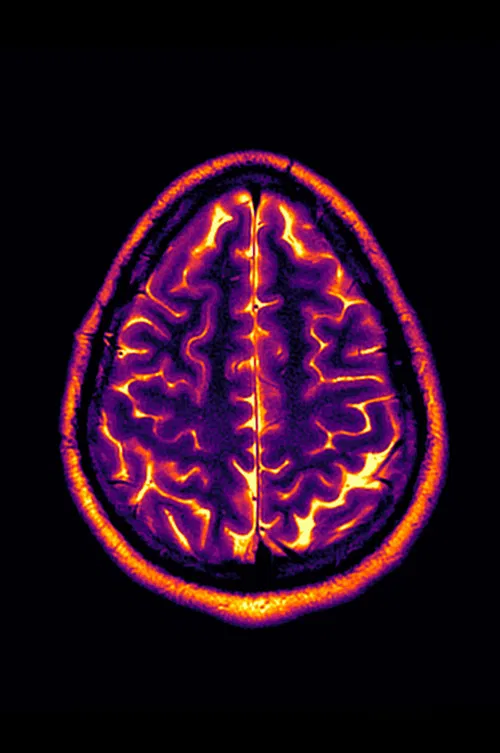

Living with a progressive disease like multiple sclerosis means annual tests and doctor’s visits, and with that comes the usual anxiety about whether this will be the year. Conclusion: Stable Disease is an experimental video made from the artist’s personal MRI image scans from 2018-2022